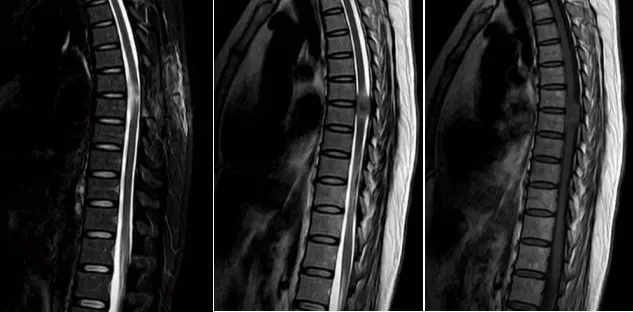

一位女性患者,11个月前没有明显诱因出现双下肢麻木、无力症状,同时伴有排便无力和间歇性跛行的情况,当时并未引起重视。一段时间后,病情逐渐加重,10天前竟严重到无法行走。为寻求治疗,患者来到我院脑外科就诊。门诊通过胸椎 MRI+增强检查发现,胸6-7椎管内左缘髓外硬膜下富血供肿瘤,再结合CT检查后,考虑脊膜瘤,于是以“椎管内占位性病变”将患者收入脑外科住院治疗。

入院后,脑外科团队积极开展术前准备工作。经过详细诊断,基本确定为椎管内肿瘤,脊膜瘤的可能性最大,决定为患者实施肿瘤切除术。术中可见肿瘤呈砂砾状,大小约1.5×2.2cm,颜色呈灰白色,血供丰富且质地坚韧,相应位置的硬脊膜增厚,脊髓受压明显且向右移位,不过幸运的是,肿瘤与脊髓并无明显粘连。在显微镜下,医护人员小心翼翼地将肿瘤分离,严密保护脊髓,最终分块将肿瘤完全切除,病理诊断结果为脊膜瘤。患者恢复良好,现已顺利出院。